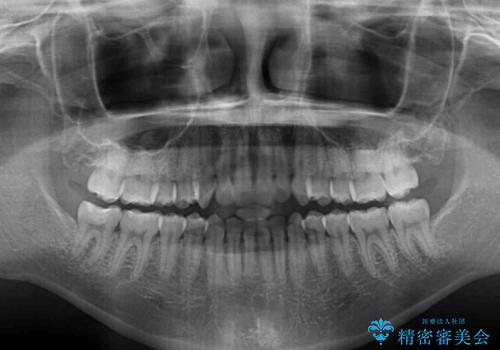

上下前歯が接触しない オープンバイトをインビザラインで改善

- 前歯の上下スペースによる食べにくさを気にして来院された患者様です。

インビザラインにより上下の前歯の隙間を閉じていくこととしました。

上下の奥歯を圧下させるようにすることで、前歯を接触させるように計画しました。

上下の隙間に舌が入り込むことがオープンバイトの原因であったため、舌の筋肉のトレーニングも並行して行い、後戻りの抑制を図りました。